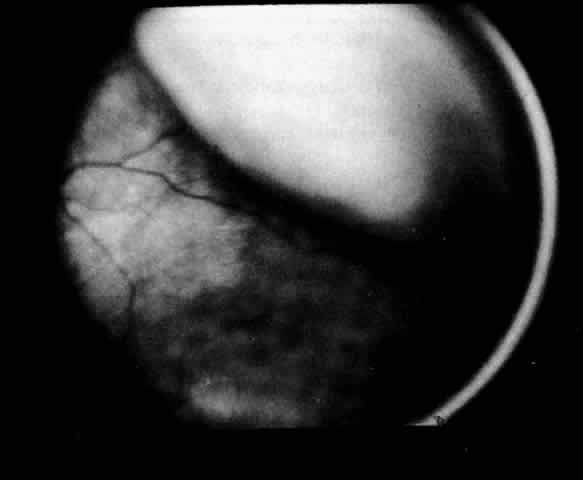

The presence of certain clinical characteristics may assist in the diagnosis of a ciliochoroidal effusion (Table 1). One clinical feature is choroidal edema. Choroidal edema may resemble a retinal detachment to a hasty observer; however, darkness of the uvea, lack of tremulousness, and normal retinal vessels indicate a probable uveal process (Fig. 1). The effusion may extend under the pars plana, allowing visualization of the ora serrata without scleral depression (Fig. 2).9 As shown in Figure 2, the surface of the elevation is convex and smooth, with a solid appearance and a homogeneous grayish color. A shallow anterior chamber and a low intraocular pressure may also suggest the diagnosis. Myopia in the presence of anterior displacement of the lens-iris diaphragm may be another diagnostic clue.10,11

Fig. 2. The ora serrata is visible in the pupillary space due to a ciliochoroidal effusion that developed after retinal detachment surgery in an aphakic eye. The arrow indicates the ora bay. (Courtesy of Retina Service, Wills Eye Hospital, Philadelphia)

Fig. 5. Flat ciliochoroidal effusion. The ora serrata is visible without scleral depression in a patient with Schepens-Brockhurst syndrome. The arrow indicates the ora bay.